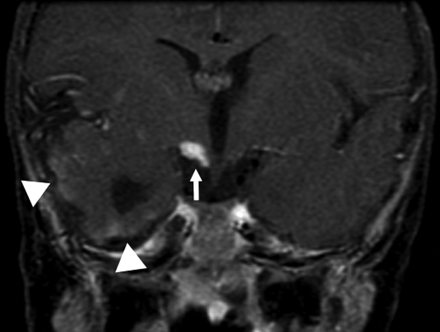

Additional cerebrovascular anomalies included the absence of the ipsilateral ICA (n = 2), aneurysms (n = 2), narrowing of the ICA (n = 4), and narrowing of basilar artery (n = 1). Two patients exhibited interval changes of their cerebral vasculature on the basis of repeat imaging. One patient had regression of a left posterior cerebral artery P3 segment aneurysm demonstrated on serial conventional angiography. The other patient had progressive narrowing of the proximal ICAs bilaterally and developed a fusiform aneurysm on subsequent MRAs. Intracranial vascular lesions were detected by contrast MR imaging in 2 patients. One patient had leptomeningeal enhancement involving the anterior pons and the superior cerebellum ipsilateral to the hemangioma. The other patient had similar enhancement along the temporal lobes as well as having an enhancing nodular mass isointense to the hemangioma anterior to a cerebral peduncle (Fig 5). Sixty-seven percent (8/12) of patients with cerebrovascular anomalies had underlying CNS structural malformations.

Postcontrast coronal T1-weighted image of the brain again demonstrates the abnormally enhancing mass (arrow) just below right-sided portions of the hypothalamus. Vague surface enhancement along the right temporal lobe is noted (arrowheads).